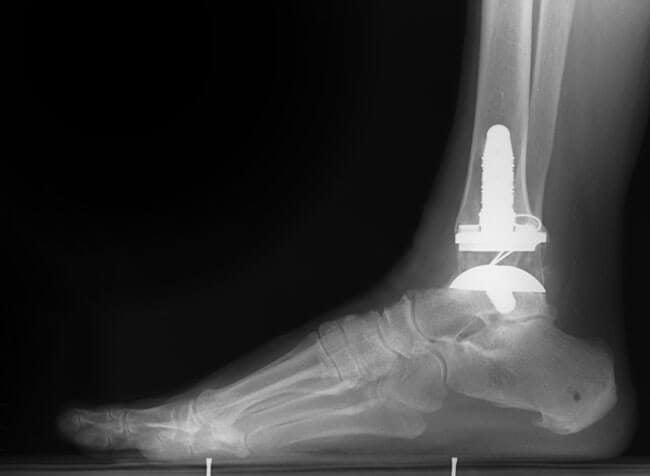

Хирургическое лечение

Эндопротезирование голеностопного сустава – перспективное, но мало изученное направление. Реконструкция этой части опорно-двигательного аппарата, как бы хорошо она ни была проведена, все равно потенцирует возникновение вторичного деформирующего артроза. Риск осложнения – результат следующих факторов:

Клиническое наблюдение в больницах Европы позволило сделать вывод, что на протяжении длительного времени использования хорошо зарекомендовали себя эндопротезы марки S.T.A.R. производства фирмы WALDEMAR LINK GmbH & Co. KG (Германия), Mobility™ (DePuy, Англия), марки HINTEGRA (New Deal SA, Франция).

У 15 пациентов со сроком наблюдения 6,2 года удалось установить признаки нестабильности и преждевременного износа компонентов протеза. Выполненное исследование показало: наибольшая выживаемость эндопротеза – у пациентов с ревматоидным артритом и у лиц со сниженной двигательной активностью.

Преимущества современных эндопротезов:

- Костный цемент, применяемый в процессе фиксации, не выдавливается за пределы эндопротеза при его установке.

- Усовершенствованные модели имплантов исключают необходимость проведения резекции значительной площади суставных поверхностей. Учитывая этот фактор, губчатая кость представляет собой достаточно надежную опору для закрепления костного цементного материала.

- Не происходит перемещения имплантатов. Протез не мигрирует в дистальный метаэпифиз большеберцовой кости или тело таранной кости.

- Хирургическая травма не провоцирует слабое заживление послеоперационной раны.

- Минимальное число неблагоприятных исходов.

Интерес к эндопротезированию голеностопного сустава вернулся сразу после внедрения бесцементных имплантатов, совершенствования дизайна (стали практиковать имплантацию трехкомпонентных моделей), нормализации качества операционного инструментария.